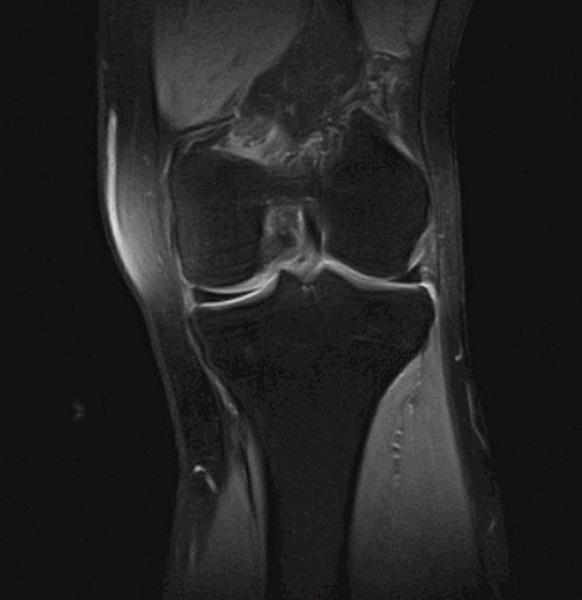

Фронтальный срез МРТ коленного сустава

Все эти изменения наиболее выражены в средней части суставной поверхности, так как она сильнее нагружена. Уменьшение эластичности хряща приводит к тому, что он уже не защищает подлежащую кость, формируется остеосклероз. Также возможно появление кист, которые вскрываются, образуя костные эрозии. На боковых участках суставных поверхностей хрящ компенсаторно разрастается и замещается костной тканью – образуются остеофиты.